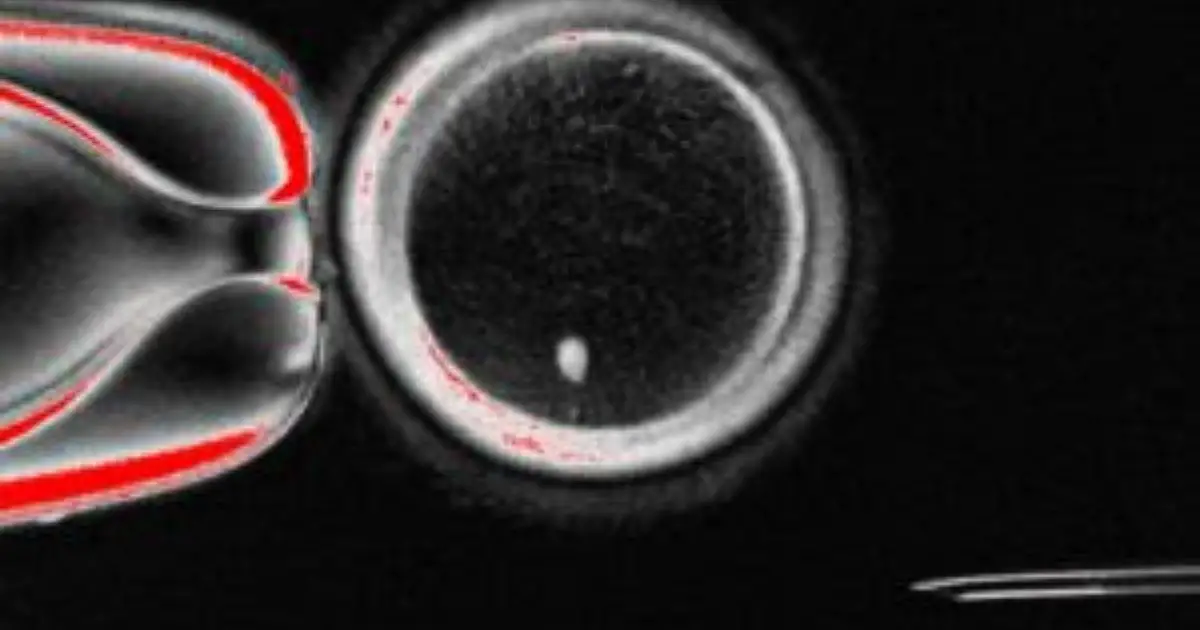

Le cellule della pelle umana possono essere trasformate in ovuli fecondabili, aprendo nuove interessanti prospettive per i trattamenti dell’infertilità. Questo curioso risultato emerge da uno studio, pubblicato sulla rivista Nature Communications, condotto dagli scienziati del Center for Embryonic Cell and Gene Therapy e della Division of Reproductive Endocrinology and Infertility presso la Oregon Health & […] L'articolo “Ovuli fecondabili dalle cellule della pelle”, lo studio su Nature. Gli scienziati: “Concetto sperimentale contro l’infertilità” proviene da Il Fatto Quotidiano.